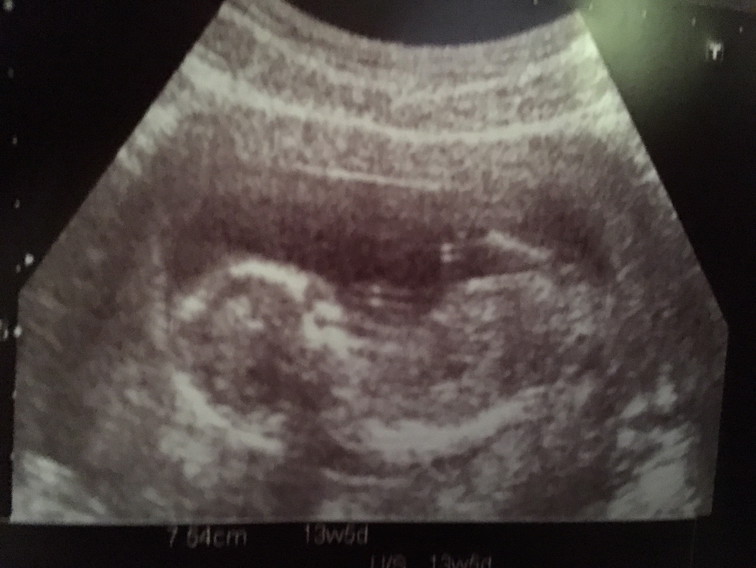

แม่ๆคนไหนมีภาพอัลตร้าซาวด์ประมาณ13วีคบ้างคะ ของเรา13วีค ภาพแบบนี้ค่ะ ดูไม่ออกเลย?

13w ค่ะ